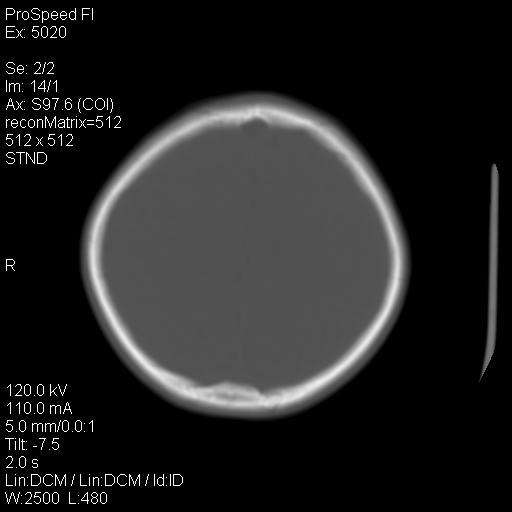

标题: PED1637:M 6Y 顶部无痛性包块两月。 [打印本页]

标题: PED1637:M 6Y 顶部无痛性包块两月。

2、颅骨局部缺失,边缘光滑、整齐

颅骨的病损表现为内外颅骨板层不规则的锋利的破坏,形成“斜边缘”,有一定的特点

颅骨为好发部位,生长缓慢,常位于顶骨、枕骨及颞骨,表现为颅骨缺损,呈圆形或椭圆形,边界清,无硬化